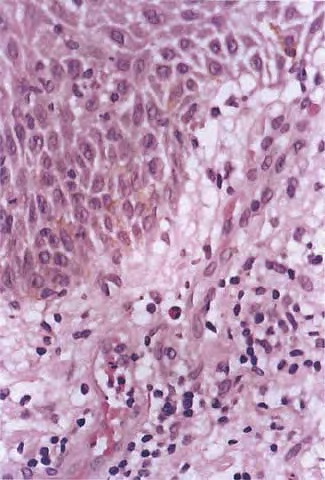

Acute contact dermatitis = التهاب ا لجلدالحاد بالتماس